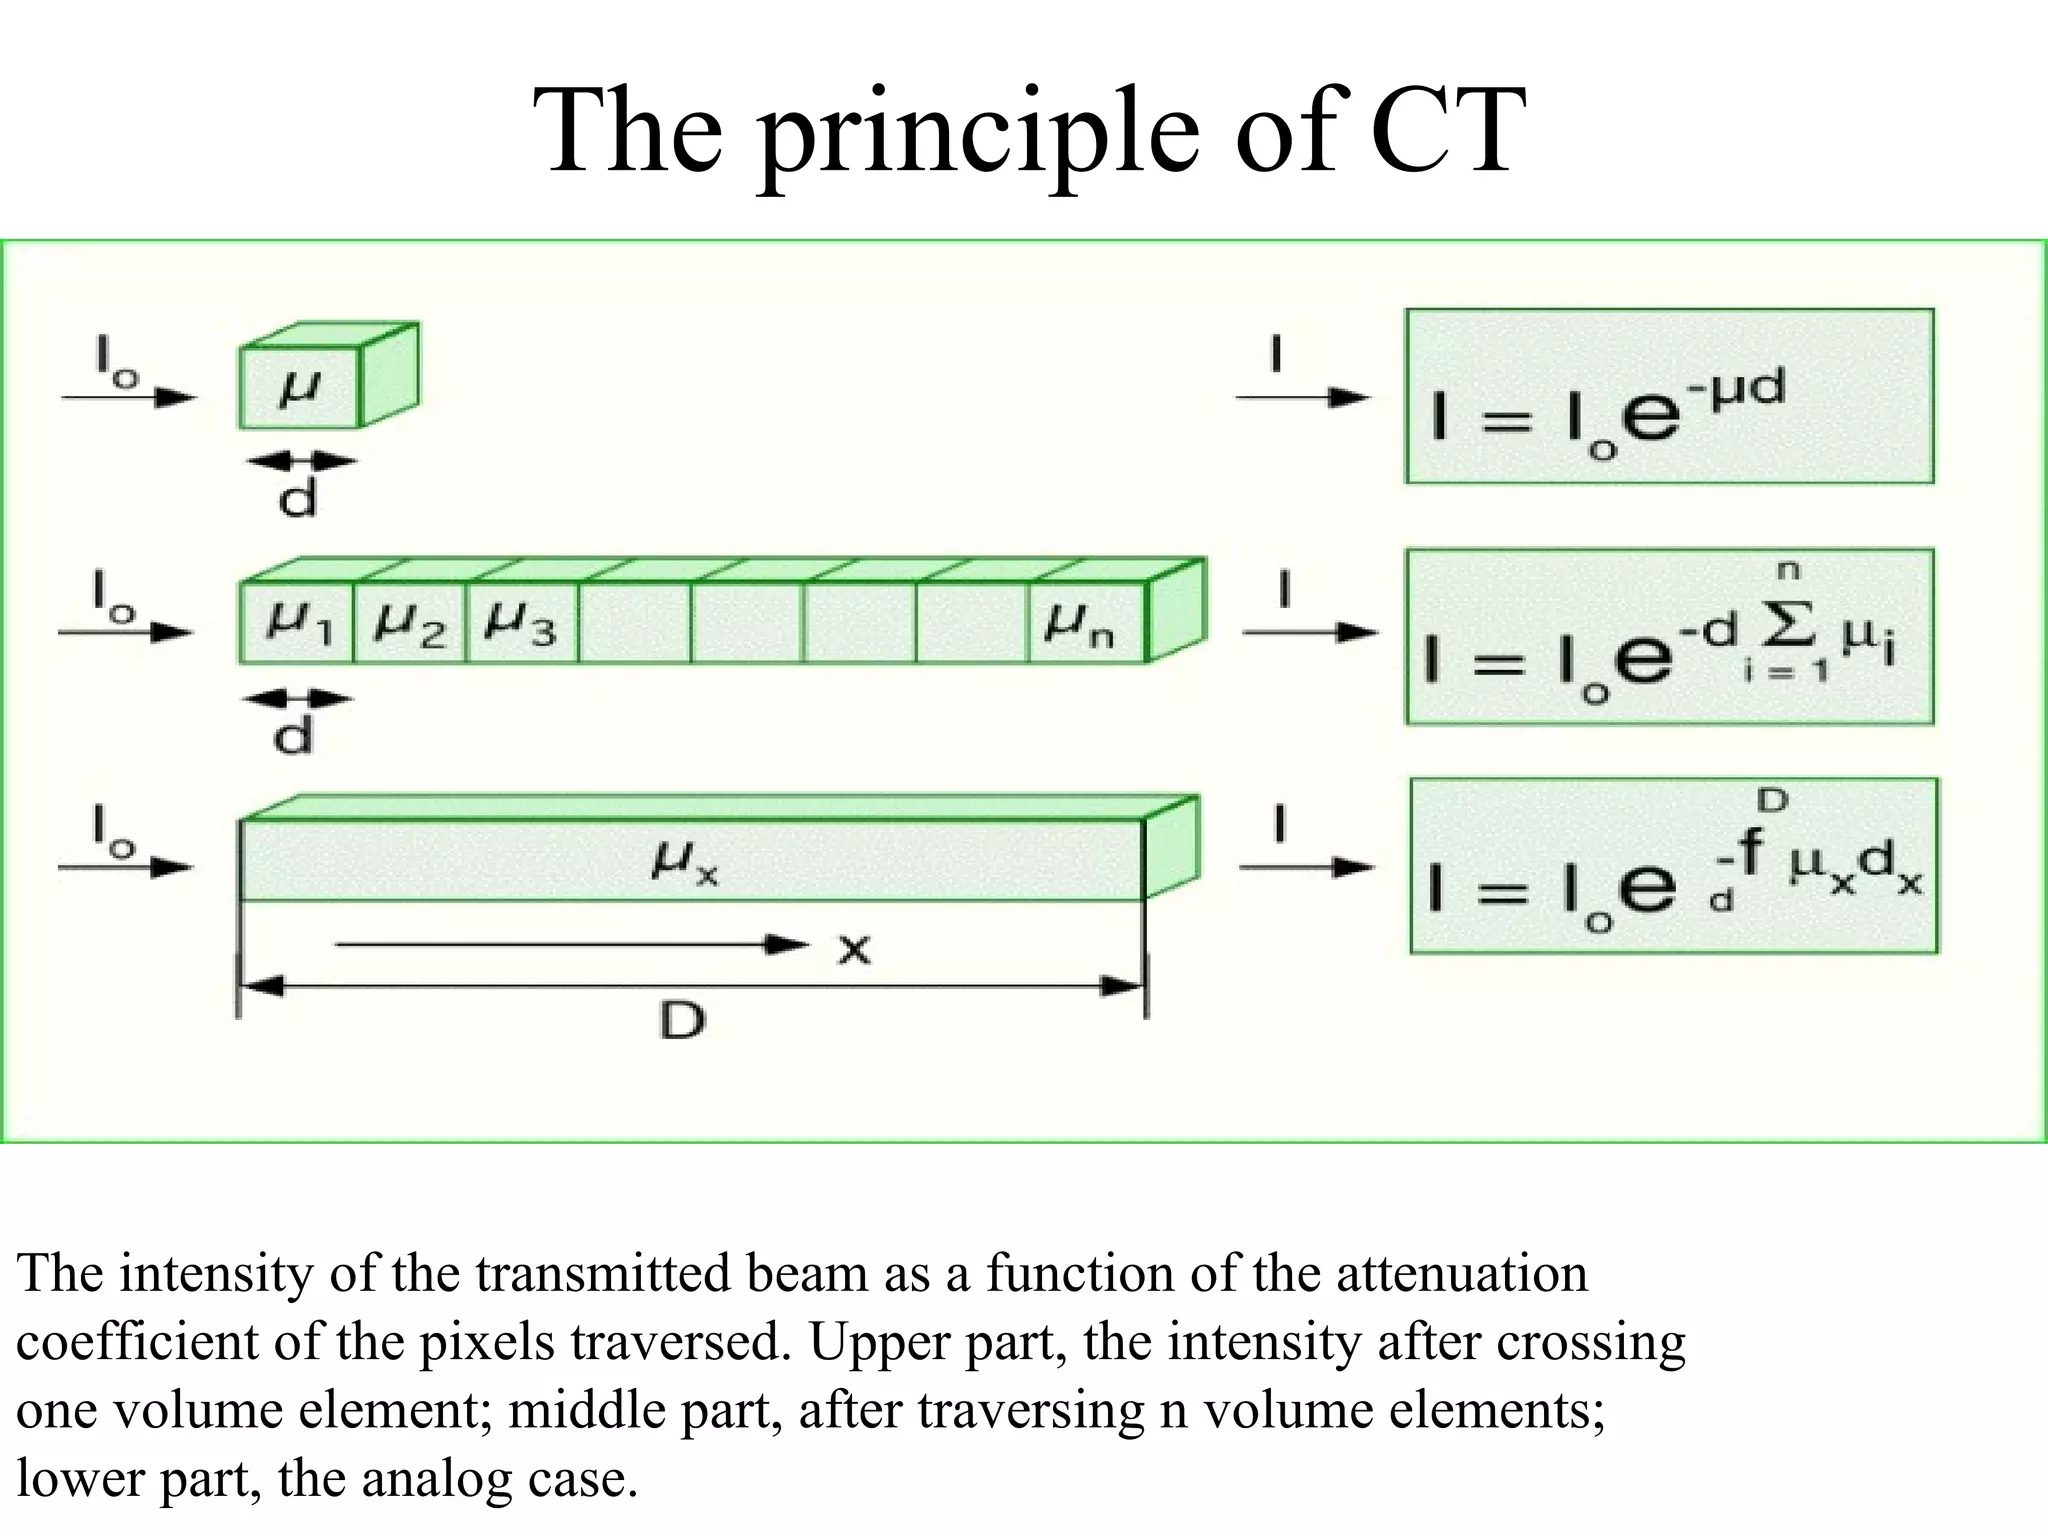

The document discusses various medical imaging modalities including x-rays, computed tomography (CT), and digital mammography. It describes the basic principles and historical development of these technologies, how images are formed, and what types of anatomical features and abnormalities they can detect. Key advances include the development of digital systems that allow image manipulation and remote consultation. While promising, digital mammography still faces challenges around resolution and cost.